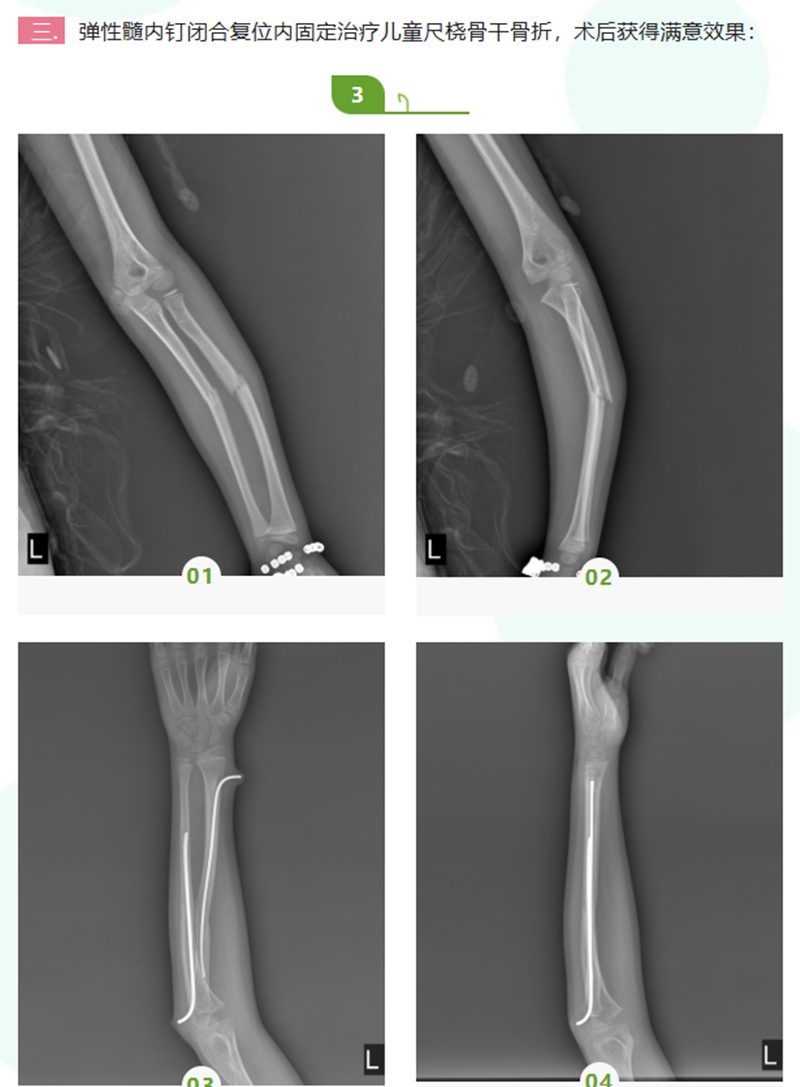

我科目前开展的骨科新技术项目包括:创伤骨科:交锁髓内钉内固定治疗四肢长骨干骨折、股骨近端髓内钉(PFNA、intertan)治疗股骨粗隆间骨折、经皮微创接骨板技术(MIPO)治疗胫腓骨骨折、弹性髓内钉闭合复位治疗儿童四肢骨折等,上述微创技术在四肢骨折中的运用均符合生物学原则,具有创伤小、术中出血少、术后恢复快等优点;关节外科:人工半髋及全髋关节置换术、人工全膝关节置换术、膝关节镜下半月板成形术及交叉韧带重建术等;脊柱外科:开展经皮椎间孔镜下治疗腰椎间盘突出症、经皮椎体后凸成形术微创治疗老年骨质疏松性椎体压缩性骨折、颈椎前路手术治疗混合型颈椎病等;显微外科手术:肌腱、血管吻合术、断肢(指、趾)再植术等。其中髓内钉及MIPO技术、人工全膝及全髋关节置换术、关节镜手术及手足显微外科手术均在我院率先开展,居于领先水平。